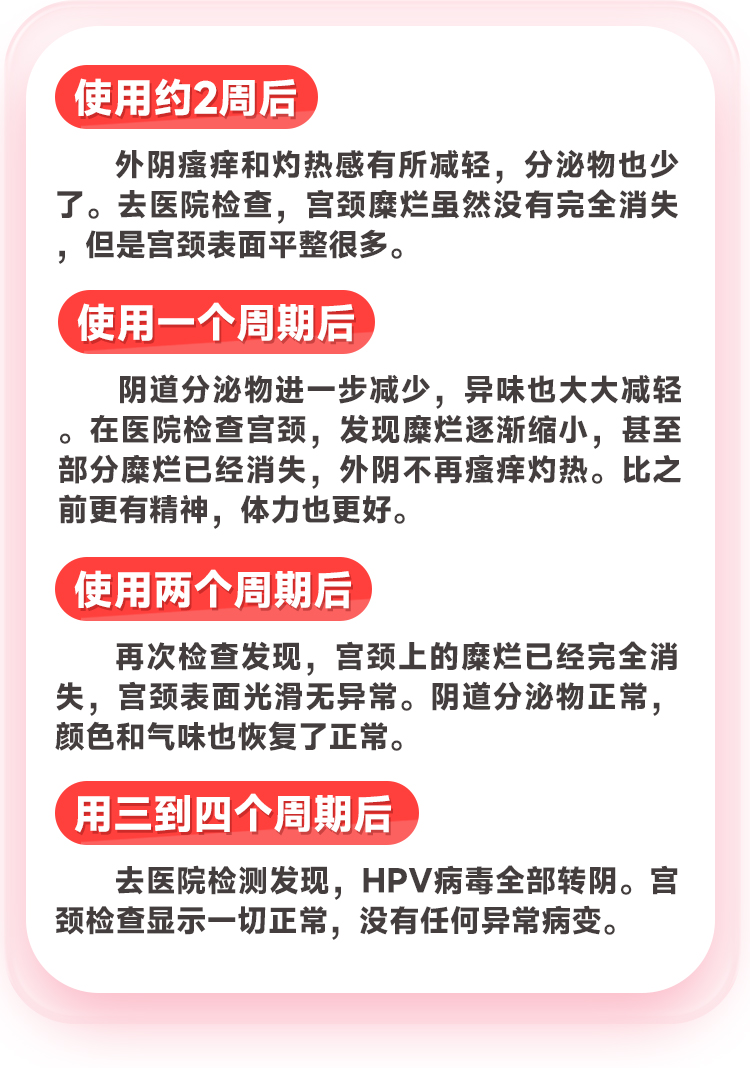

以下是我用了三个周期的具体变化

我整理出来大家可以对照看一下: